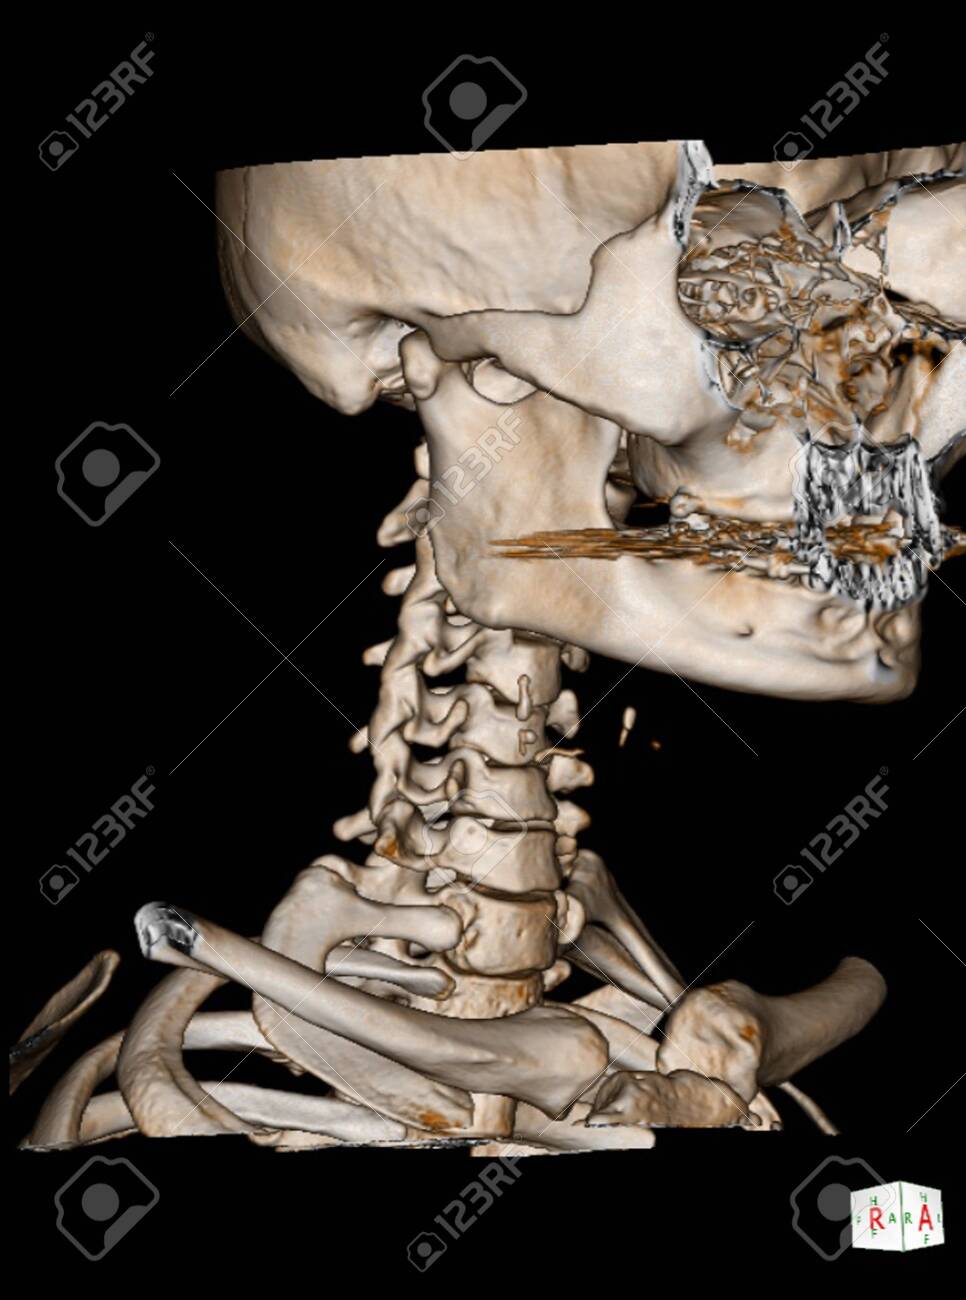

28+ Skull Base Ct Anatomy . 2.1 skull base anatomy—anterior and middle surgical anatomy pearl. The bregma is the point where joins coronal suture and sagittal suture. Middle Skull Base Plastic Surgery Key from plasticsurgerykey.com The skull is a bony structure that supports the face and forms a protective cavity for the brain. This view may expose some daunting anatomy, but it is not difficult to learn once you associate the various structures with a function and in that way store all the informations into your. 2.1 skull base anatomy—anterior and middle surgical anatomy pearl. The sphenoid bone is a single, complex bone of the central skull (). Skull base anatomy and cranial nerves explained in a simple way to remember it and use it in your daily practice as a radiation. It shows the thin cortical margins of skull base neurovascular foramina. Inferior view of base of the skull. The ...

25+ Skull Base Ct Anatomy Radiology . The sagittal suture is the line where the right and left parietal bone are in contact. The skull has inner and outer tables of cortical bone with central cancellous bone called 'diploe'. Chondrosarcoma Of Skull Base Grade Ii Radiology Case Radiopaedia Org from prod-images-static.radiopaedia.org The skull base can be evaluated by computed tomography (ct), which will demonstrate the bony structures of the skull base with its foramina and fissures for vessels and cranial nerves, the temporal bone, and sinonasal cavities. Base of the skull | radiology reference article. A brief introduction to acute vs chronic subdural. In such a situation, the carotid artery would run through a. Yale radiology and biomedical imaging. Brain, bones of skull, paranasal sinuses. Basic gross anatomy of the human heart. Radiological anatomy is crucial for radiolog...